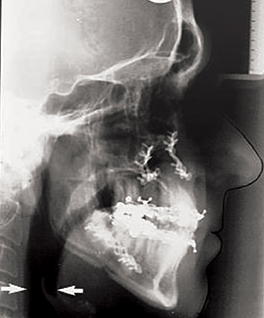

The role of maxillomandibular advancement surgery in obstructive sleep apnoea

Facial surgery for the correction of acquired or developmental skeletal and occlusal abnormalities has been practised within the scope of oral and maxillofacial surgery (OMFS) for several decades. OMFS surgeons have an understanding of the influence of skeletal movements on...